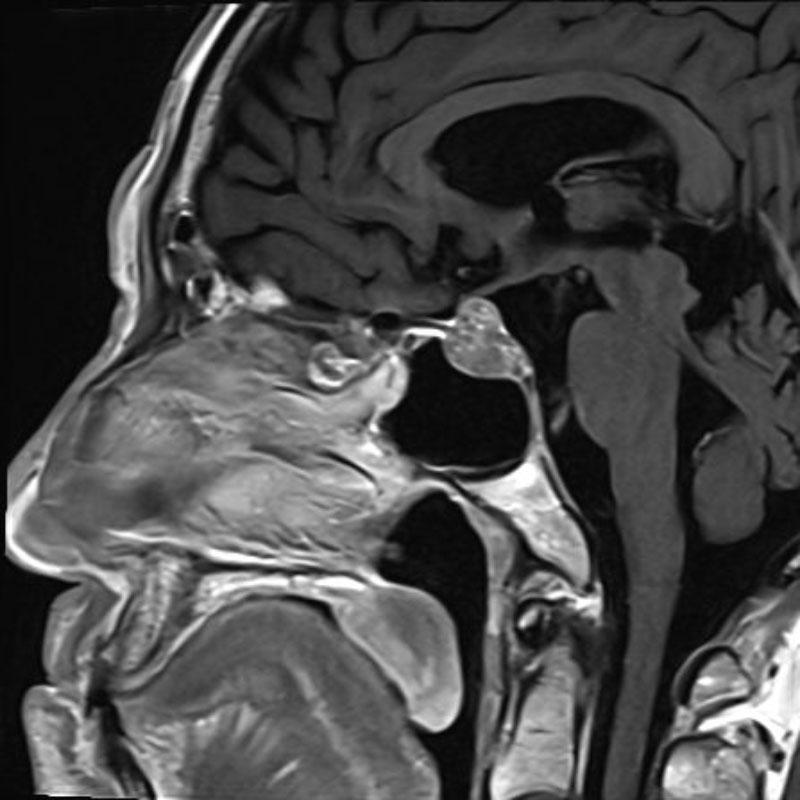

頭蓋咽頭腫

頭蓋内腫瘍摘出術

No.’25_96 手術前1

No.’25_96 手術前2